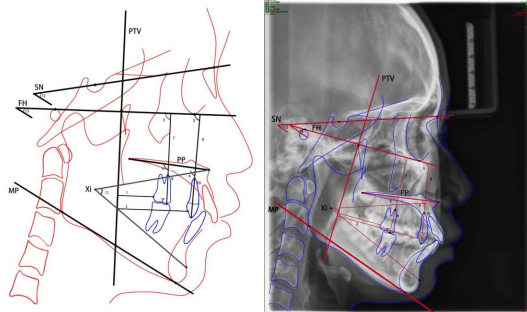

扩大治疗适应症范围,给本不需要矫治的儿童戴入矫治器,不仅剥夺了孩子快乐的童年,而且可能造成多种不良后果。例如,盲目扩弓导致第一磨牙严重颊倾,造成长期咬合紊乱;排齐拥挤的前牙后,占据间隙,造成尖牙无法萌出。特别是部分商家的成品或半成品矫治器被推崇为“神器”,是否存在其宣称的适应症和相应效果,口腔正畸学界尚有不同的观点,家长们请谨慎选择。最终是否可以进行治疗还需根据头影测量、模型分析、CBCT数据等决定。

贯穿正畸治疗的头影测量分析。(引自蔡国鑫.尖牙后移时应用种植支抗与横腭杆支抗的比较[J].汕头大学医学院学报,2022,35(3):145-149.